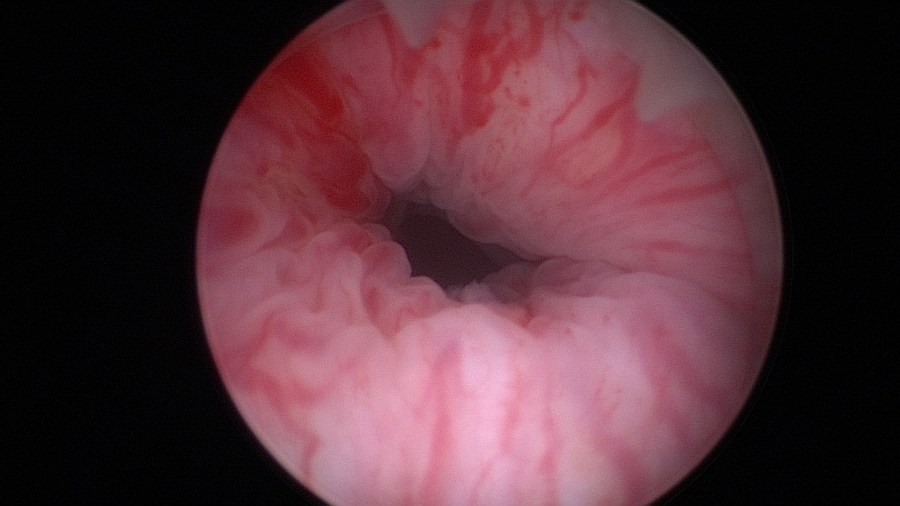

Beginn with a thorough cystoscopy. Patients that have incontinence recurrence should be examined for sling or even suture erosion. Watch out for tumors or stones.

The bladder neck.

The mid-urethra.